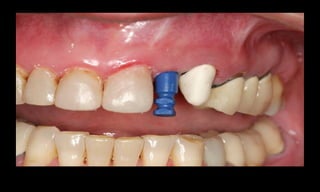

Cicatrizador

CM